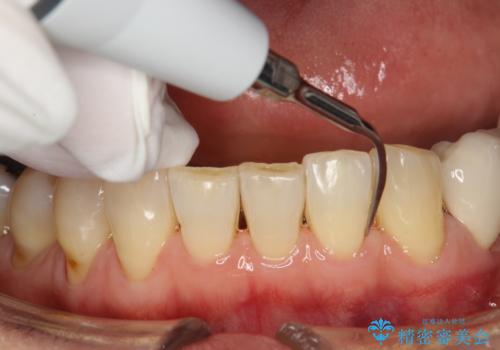

- すき間の部分の歯磨きがしずらく、クリーニング希望で来院されました。今後はセラミックによる治療を考えてとの事でした。PMTC(保険外治療)30分コースを行いました。

PMTC(保険外治療)とは、歯垢・歯石・着色などを除去することです。磨きのこしなどにより歯垢が付着し続けると、歯石に変化していきます。歯石になってしまったら、歯ブラシだけで落とすことができなくなります。そのため歯科医院での専門的な機械・材料を使用してのクリーニングが必要です。